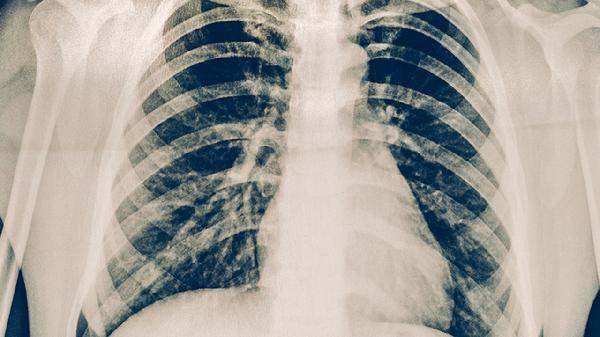

肺炎支原体通过其黏附蛋白损伤呼吸道上皮,引发间质性肺炎。典型表现是阵发性的干咳和头痛,胸部X光可见斑片状阴影。大环内酯类抗生素,如阿奇霉素,通常是首选药物,疗程一般为2到3周。